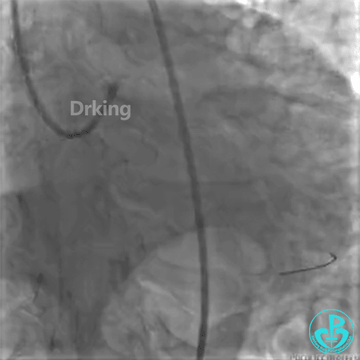

以下是导丝成功通过严重扭曲病变的图:

把Sion导丝送至高位OM的远段,在双腔微导管的辅助支撑下,把BMW导丝通过LCX扭曲及病变处顺利送至远段,撤出双腔微导管,2.0×20mm球囊对病变处PTCA后狭窄减轻,于病变处植入2.75×23mm支架一枚,后分别用2.75×12mm、3.0×12mm球囊对支架内后扩,复查造影原病变处狭窄消失,TIMI血流三级。